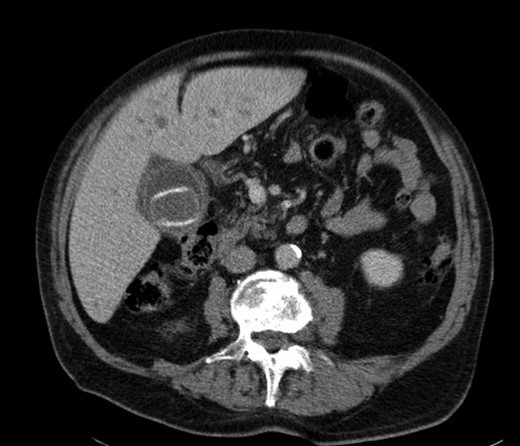

A 92-year male, with no significant co-morbidities apart from peptic ulcers, was admitted with 6 days of obstination. On examination he was dehydrated, with a hugely distended abdomen but no signs of peritonitis. Blood showed features of dehydration and plain abdominal X-ray demonstrated both small and large bowel dilatation, but no obvious causal pathology. A contrast-enhanced computed tomography scan revealed a 2.5-cm partially calcified gallstone impacted at the descending colon-sigmoid junction (Fig. 1). There was no stricture or diverticular disease distal to the stone. A cholecysto-colic fistula could be seen (Fig. 2), with a further smaller gallstone in the caecum (Fig. 3). The offending gallstone could be seen incidentally in the gallbladder on imaging 3 years previously (Fig. 4).

Large gallstone impacted in the descending colon-sigmoid junction, causing large bowel obstruction proximally.